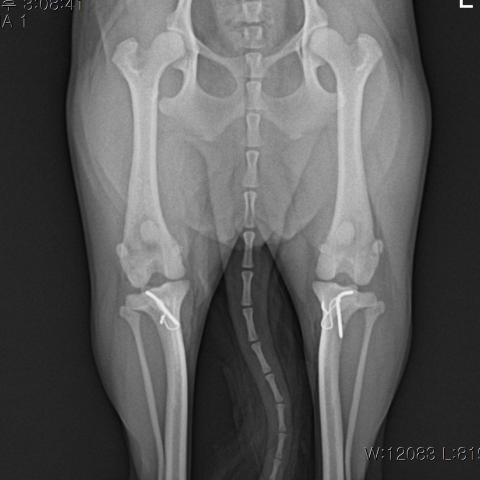

½½°³°ñ Å»±¸ ¼ö¼ú ÈÄ